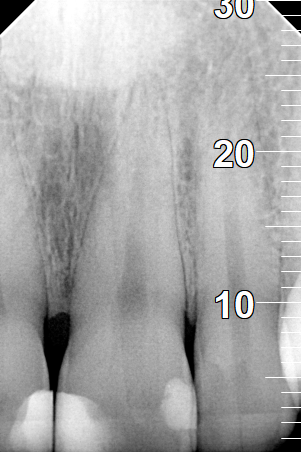

Root canal treatment

BEFORE

AFTER